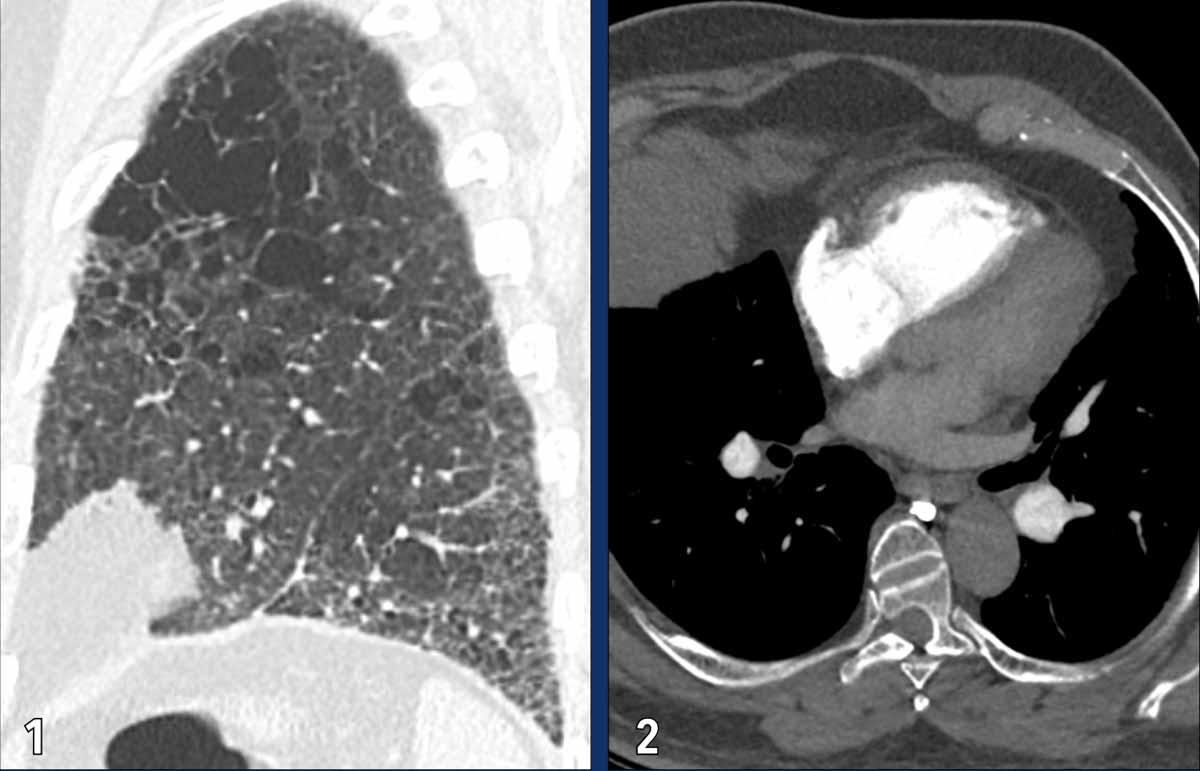

Tăng áp phổi do bệnh lý phổi

Tăng áp phổi thứ phát do bệnh phổi mạn tính và/hoặc tình trạng thiếu oxy được phân loại vào Nhóm 3 theo WHO. Bệnh lý này là hệ quả của cả những thay đổi cấu trúc lẫn chức năng trong hệ mạch máu phổi, xuất phát từ bệnh lý phổi nền. Trong bối cảnh đó, các mạch máu phổi nhỏ có thể bị mất đi hoặc trải qua quá trình co mạch và tái cấu trúc, dẫn đến giảm diện tích giường mạch máu và làm tăng áp lực động mạch phổi.

Các nguyên nhân thường gặp bao gồm bệnh phổi tắc nghẽn mạn tính (COPD) và xơ phổi. Ngưng thở khi ngủ do tắc nghẽn và tình trạng tiếp xúc mạn tính với môi trường thiếu oxy ở vùng núi cao cũng có thể đóng vai trò trong sự phát triển của bệnh.

Hình ảnh

Bệnh nhân này có sự kết hợp giữa

khí phế thũng và xơ phổi.

Tình trạng giãn và phì đại thất phải, cùng với dấu hiệu phẳng vách liên thất là hệ quả của tăng áp phổi.